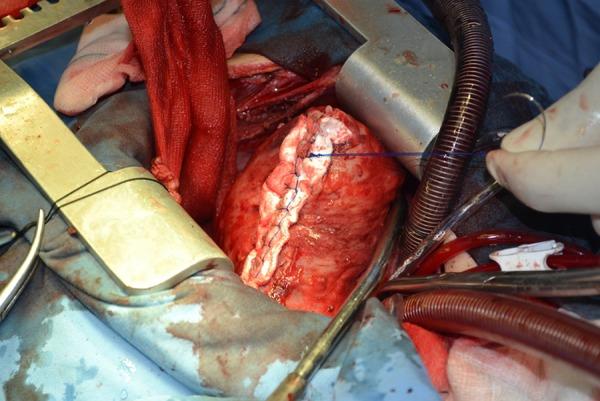

A 13-year-old boy with dyspnea and atypical pericardial type chest pain for three months was referred to us. Chest X-ray revealed linear calcification in the left side of the heart. Computed tomography demonstrated a cyst with peripheral calcification and without internal septation in the lateral left ventricle (LV) myocardium. Serologic IgG test was positive for Echinococcosis. No other cyst was seen in the other organs such as the lungs and liver. By midline sternotomy on pump, an incision was made 2-cm lateral to the left ascending artery through the LV myocardium and without entering any cardiac chamber. After injecting hypertonic (5%) saline, the cyst was punctured and its fluid contents were aspirated, the cyst was enucleated, and the cavity marsupialization was done for protection of the myocardium. LV ejection fraction before operation was 40% but after operation and repairing LV myocardium, ejection fraction increased to 50% in. Histopathologic examination confirmed a hydatid cyst.

一名13岁男孩因呼吸困难和非典型心包型胸痛3个月被转诊至我院。胸部X线显示心脏左侧有线性钙化。计算机断层扫描显示左心室(LV)外侧心肌有一个周边钙化且无内部间隔的囊肿。血清学IgG试验棘球蚴病呈阳性。在肺和肝等其他器官未发现其他囊肿。通过在体外循环下进行正中胸骨切开术,在左升主动脉外侧2厘米处经左心室心肌做一个切口,且不进入任何心腔。注入高渗(5%)盐水后,穿刺囊肿并吸出其内容物,将囊肿摘除,并对腔隙进行袋形缝合以保护心肌。术前左心室射血分数为40%,但术后修复左心室心肌后,射血分数增至50%。组织病理学检查证实为包虫囊肿。